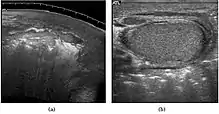

Sonography of a normal testis. The normal testis presents as a structure having homogeneous, medium level, granular echotexture. The mediastinum testis appears as the

hyperechoic region located at the periphery of the testis as seen in this figure. | |

The normal adult testis is an ovoid structure measuring 3 cm in anterior-posterior dimension, 2–4 cm in width, and 3–5 cm in length. The weight of each testis normally ranges from 12.5 to 19 g. Both the sizes and weights of the testes normally decrease with age. At ultrasound, the normal testis has a homogeneous, medium-level, granular echotexture. The testicle is surrounded by a dense white fibrous capsule, the tunica albuginea, which is often not visualized in the absence of intrascrotal fluid. However, the tunica is often seen as an echogenic structure where it invaginates into the testis to form the mediastinum testis. In the testis, the seminiferous tubules converge to form the rete testes, which is located in the mediastinum testis. The rete testis connects to the epididymal head via the efferent ductules. The epididymis is located posterolateral to the testis and measures 6–7 cm in length. At sonography, the epididymis is normally iso- or slightly hyperechoic to the normal testis and its echo texture may be coarser. The head is the largest and most easily identified portion of the epididymis. It is located superolateral to the upper pole of the testicle and is often seen on paramedian views of the testis. The normal epididymal body and tail are smaller and more variable in position.